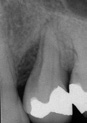

Patientenfall (Abb. 1 bis 8)

Aufgrund einer fortgeschrittenen parodontalen Erkrankung und eines schweren Knochenverlustes rund um den infizierten Zahn, musste der obere Prämolar des Patienten extrahiert werden. Im posterioren Oberkiefer wurde ein intraalveolärer Knochendefekt der Klasse I diagnostiziert, ohne eine Dehiszenz oder einen Fenestrationsdefekt vorzuweisen.

Dieser Patient wurde bereits im Jahr 1991 behandelt. Der Fall zeigt eine der ersten klinischen Anwendungen von Geistlich Bio-Oss Collagen. Aufgrund des intraalveolären Knochendefekts wurde eine Frühimplantation mit gleichzeitiger Augmentation durchgeführt. Die Implantation wurde 6 Wochen nach Extraktion des Prämolars vorgenommen. In der postoperativen Phase erfolgte eine unauffällige Weichgewebeheilung nach Extraktion. Für die Implantatinsertion wurde der Frühimplantationsansatz mit einer Heilungsphase von 6 Wochen gewählt. Die Knochenaugmentation wurde gleichzeitig mit der Implantatinsertion durchgeführt. Das Implantat wurde nach der Lappenpräparation an einer Stelle mit einem schweren Knochendefekt eingesetzt.

Für den Knochenaufbau wurde Geistlich Bio-Oss Collagen in den Defekt appliziert und nach der Augmentation die Eingriffsstelle mit einem Kollagenvlies abgedeckt. Weitere 6 Monate nach dem Eingriff wurde die endgültige Kronenrestauration eingesetzt. Bei der weiteren Nachuntersuchung nach nunmehr 25 Jahren zeigte die Röntgenaufnahme ein stabiles Implantatlager und das klinische Bild bei der Nachkontrolle einen ästhetischen Zahnstatus.